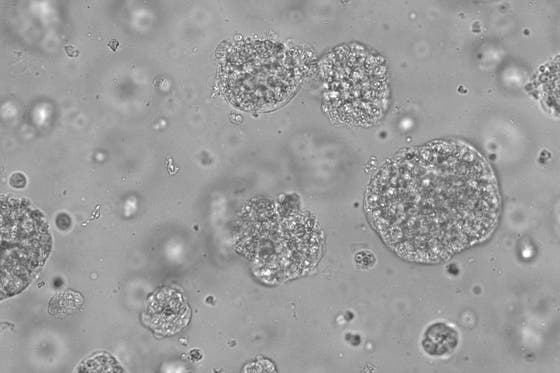

Read moreKarin Gerritsen ontvangt subsidie voor nier-op-een-chip

Nefroloog Karin Gerritsen van het UMC Utrecht ontvangt een subsidie van 1,8 miljoen euro voor het onderzoek NanoKid van NWO. In dit onderzoek werkt ze aan een innovatieve nier-op-een-chip: een miniatuurmodel waarin de belangrijkste nierfuncties worden nagebootst. Het uiteindelijke doel is om deze nier-op-een-chip te gebruiken als fundamentele bouwsteen voor een bioartificiële nier en het verbeteren van niervervangende therapieën.